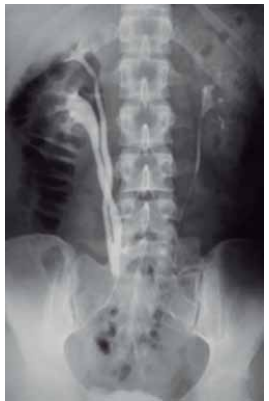

Exames contrastados do sistema urinário utilizam uma

substância especial, geralmente à base de iodo, que é injetada na veia. Essa substância transita na corrente sanguínea, é filtrada pelos rins e preenche o trato urinário.

O exame a seguir é conhecido por: